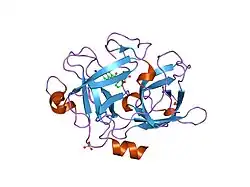

Urokinase is a 411-residue protein, consisting of three domains: the serine protease domain (consisting of residues 159–411), the kringle domain (consisting of residues 50-131), and the EGF-like domain (consisting of residues 1-49). The kringle domain and the serine protease domain are connected by an interdomain linker or connecting peptide (consisting of residues 132–158). Urokinase is synthesized as a zymogen form (prourokinase or single-chain urokinase), and is activated by proteolytic cleavage between Lys158 and Ile159. The two resulting chains are kept together by a disulfide bond between Cys148 and Cys279.[9]